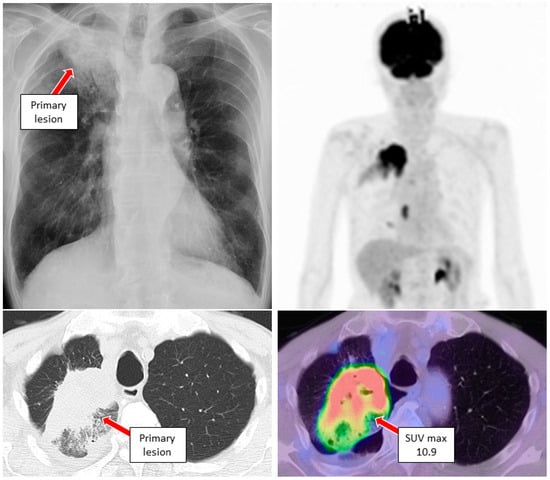

3. Case Reports